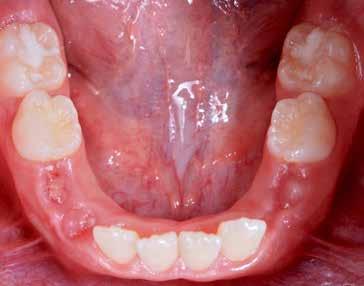

Presentazione del caso > F.V, bambino di cinque anni, presenta una malocclusione di II Classe scheletrica, III Classe dentale molare e canina destra e sinistra, morso inverso anteriore. Le arcate dentali mostrano usura degli elementi dentari anteriori a causa dell’occlusione patologica. Le linee mediane, superiore ed inferiore, sono centrate; il frenulo labiale superiore patologico per un’eccessiva estensione inter-incisale.

Dall’esame clinico si evince la III Classe dentale, l’inversione anteriore e l’over-jet negativo.

Una volta ottenuta la correzione del rapporto molare ed incisale, l’apparecchio elastodontico verrà portato dal paziente solo durante la notte per stabilizzare il risultato ottenuto e guidare l’eruzione degli elementi dentari per un totale di quattordici mesi di terapia. ad inizio trattamento :

Considerazioni > L’analisi cefalometrica ad inizio trattamento dimostra la II Classe scheletrica con protrusione del mascellare superiore e prognazia mandibolare; tendenza alla crescita verticale. L’esame clinico evidenzia una protrusione mandibolare funzionale.